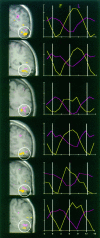

Twelve normal subjects viewed alternating sequences of unfamiliar faces, unpronounceable nonword letterstrings, and textures while echoplanar functional magnetic resonance images were acquired in seven slices extending from the posterior margin of the splenium to near the occipital pole. These stimuli were chosen to elicit initial category-specific processing in extrastriate cortex while minimizing semantic processing. Overall, faces evoked more activation than did letterstrings. Comparing hemispheres, faces evoked greater activation in the right than the left hemisphere, whereas letterstrings evoked greater activation in the left than the right hemisphere. Faces primarily activated the fusiform gyrus bilaterally, and also activated the right occipitotemporal and inferior occipital sulci and a region of lateral cortex centered in the middle temporal gyrus. Letterstrings primarily activated the left occipitotemporal and inferior occipital sulci. Textures primarily activated portions of the collateral sulcus. In the left hemisphere, 9 of the 12 subjects showed a characteristic pattern in which faces activated a discrete region of the lateral fusiform gyrus, whereas letterstrings activated a nearby region of cortex within the occipitotemporal and inferior occipital sulci. These results suggest that different regions of ventral extrastriate cortex are specialized for processing the perceptual features of faces and letterstrings, and that these regions are intermediate between earlier processing in striate and peristriate cortex, and later lexical, semantic, and associative processing in downstream cortical regions.